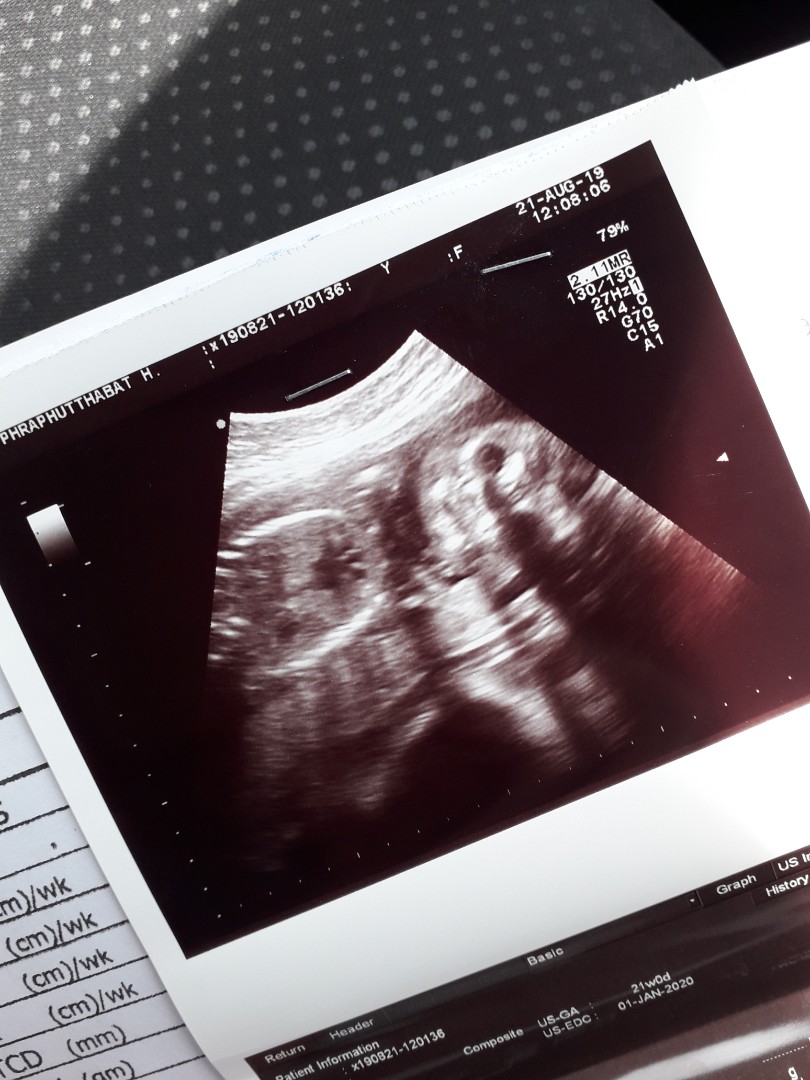

21วีค กำหนดคลอด 3ม.ค.63 ลูกชายค้า

23w ลูกชายเหมือนกันค่ะ